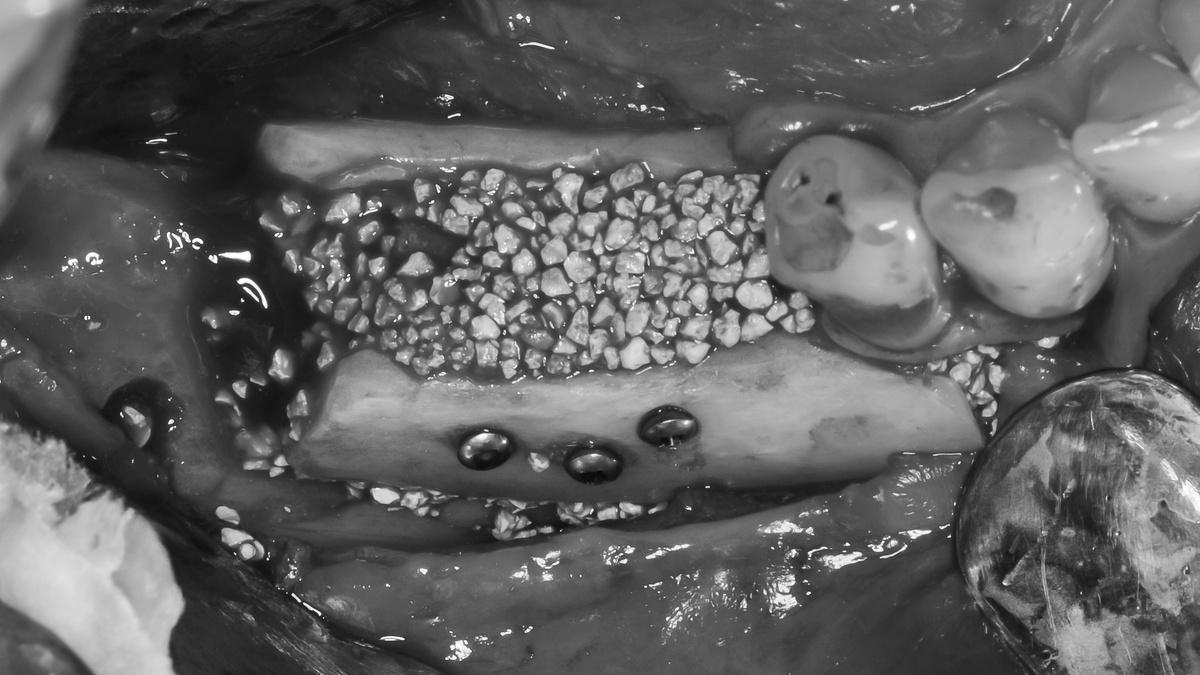

Наращивание костной ткани

Следующий шаг — реконструкция костной ткани верхней и нижней челюсти. На снимке ОПТГ обозначены области проведенной остеопластики

Верхняя челюсть

Классический «открытый» синус-лифтинг в области 5 и 6 зубов справа (№1 на снимке ОПТГ). Подготовка для будущей имплантации в этом сегменте.

Слева — комбинированный протокол— «открытый» синус-лифтинг и каркасная пластика титановой сеткой (№2 на снимке ОПТГ) для восстановления альвеолярного гребня по высоте.

-

Синус-лифтинг слева и справа провели за 1 визит

Операция длилась 4 часа, проводилась в седации

Синус-лифтинг выполнен с применением пьезохирургического аппарата

Костный материал — собственная аутокость в сочетании с натуральным костнозамещающим материалом «Bio-Oss»

Результат на снимке ОПТГ:

Результат вживую: